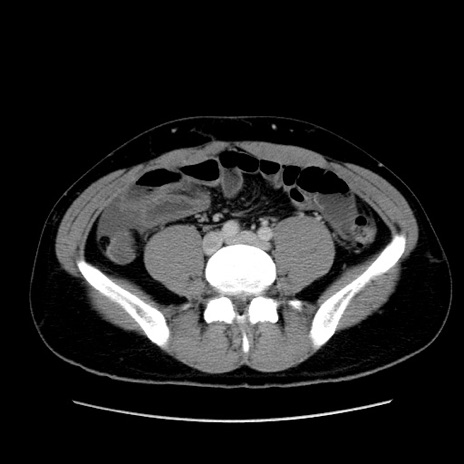

冠状断像

【症例】20歳代 男性

【主訴】心窩部痛

【現病歴】今朝より上腹部痛あり。一旦軽快していたが再度出現したため救急要請。昨日夕に白身の魚を含む刺身を食べた。

【身体所見】BP 136/89mmHg、HR 74/min、BT 37.0℃、腹部:膨満、軟、心窩部に圧痛あり。反跳痛なし、筋性防御なし、腸雑音やや亢進あり。

【データ】WBC 17700、CRP 0.48